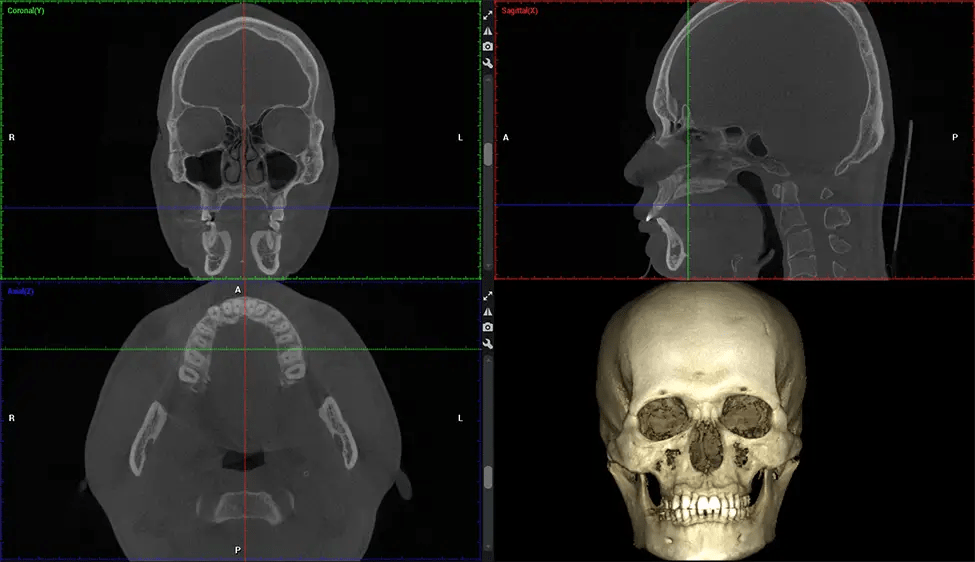

Full Skull to C7 of the Spine

Planmeca Viso G7 CBCT ( Cone Beam CT Scan ) is designed to surpass the demands of industry leaders, specialists, and large institutions. It’s has a large ø25×30 cm sensor with four built-in cameras. It can capture unlimited volume sizes from a ø3×3 cm to a ø30x30cm volume capturing the skullcap through C7 on the cervical spine. The Planmeca Viso G7 offers the industry’s largest single volume scan of ø30×19 cm. It’s poised to handle advanced imaging modalities such as Planmeca ProFace® and Planmeca 4D™ Jaw Motion technology. The occipital head support allows an unimpeded view of facial tissue.

Planmeca is the only manufacturer clinically proven to dramatically reduce patient radiation without sacrificing image quality. Planmeca Ultra Low Dose™ achieves an average reduction in dose of 77% without a statistical reduction in image quality allowing doctors to incorporate 3D imaging into routine protocols with effective patient radiation often lower than 2D intraoral imaging. This increases patient care, allows doctors to diagnose more dentistry, and often earlier in disease progression, than with 2D imaging alone.